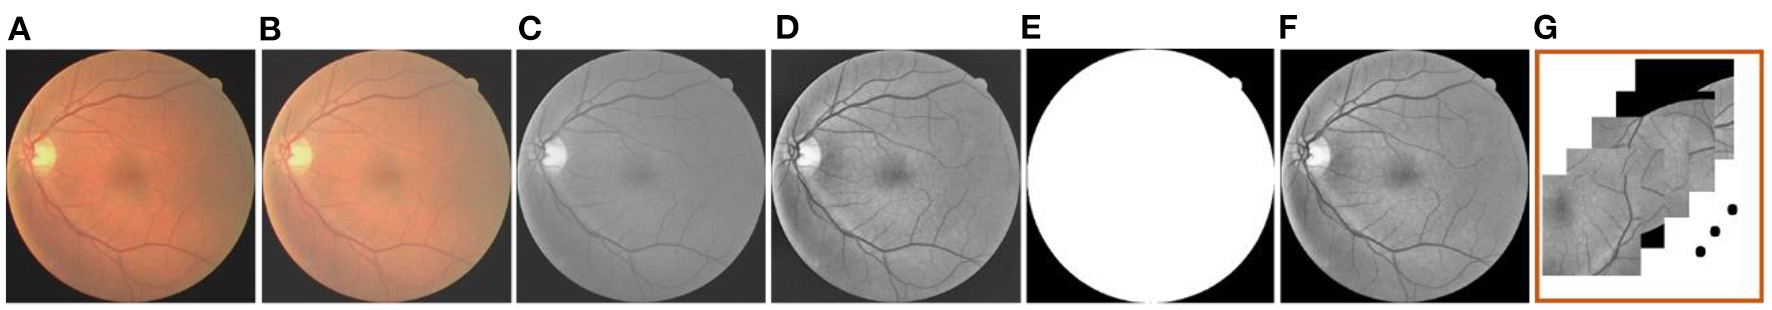

After solving the problem that transformed the vessel segmentation scene into a few-shot segmentation task, here comes the preprocessing operation. In this paper, the gamma correction and the CLAHE are employed, respectively, aiming at improving the brightness and the contrast of the retinal images. In addition, we separate the green channel, which is a routine operation in the vessel segmentation scenario, to show the vessel structures more clearly. The masks are used to eliminate the disturbance outside the region of interest. Furthermore, in response to the construction of the support and the query sets, the clipping operation is applied to the previous operation result. Meanwhile, the overlapping technique is also adopted here to ensure the similarity and the quantity of patches in the same retinal image. Specifically, we firstly set the size of the image patch template to 224 × 224 pixels, and then the clipping function is realized by moving the template in the horizontal and vertical directions. In the process, we realize the overlapping function by setting the moving step as 64 (i.e., the overlapping size is 160) among each image patches in the above directions. The whole preprocessing is shown in Figure 2.

Figure 2

The preprocessing operation: (A) Original image; (B) Gamma-corrected image; (C) Green channel image; (D) CLAHE image; (E) Mask; (F) Mask-processed image; and (G) Patches.